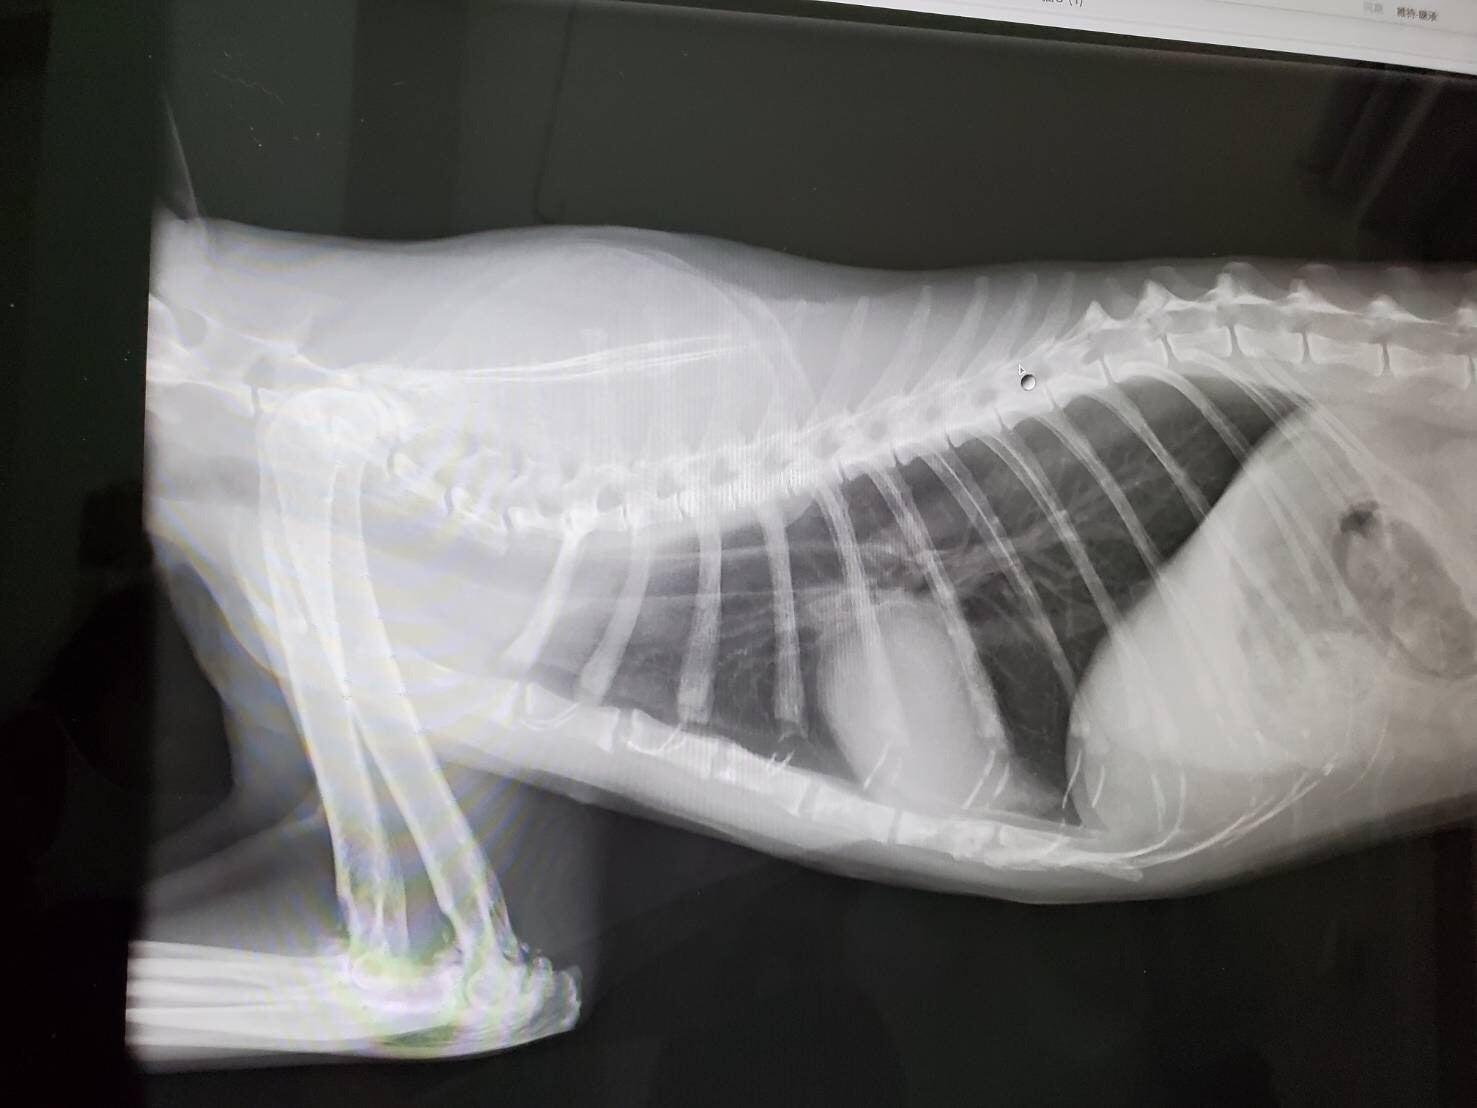

レントゲンで見ると少し肝臓の腫れがあります。

肘の老化もあり痛みがあるはずらしいのですが、感じない猫もいるそうです。」